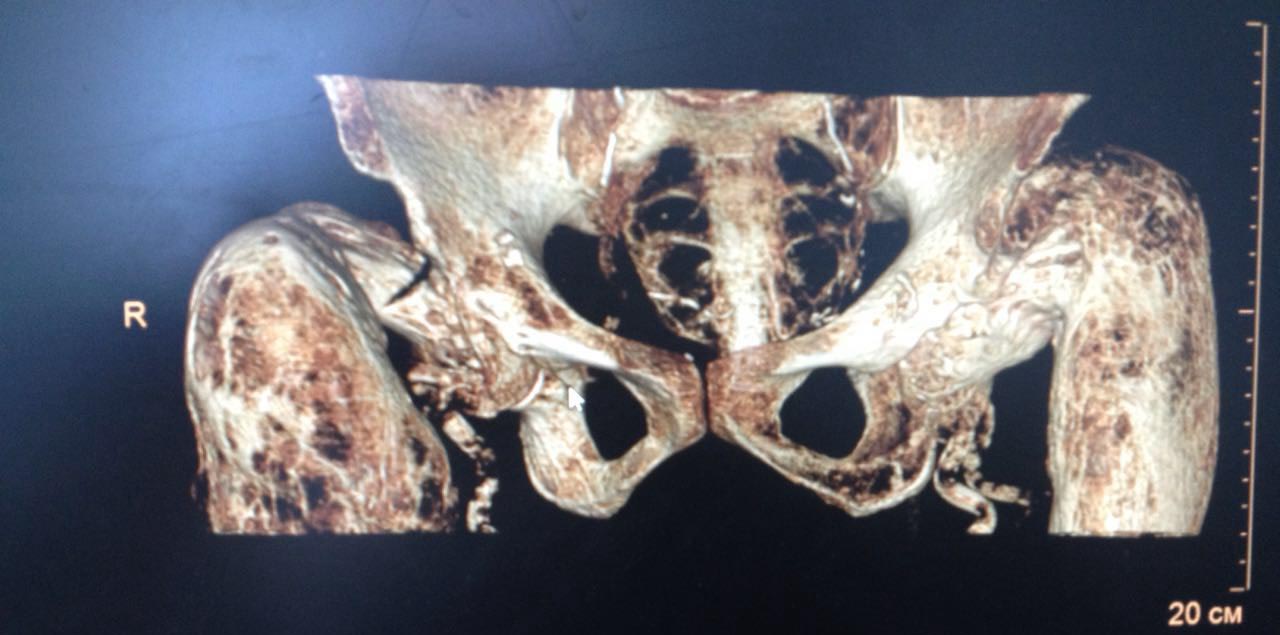

Пациентка Н. 1940 года рождения поступила в стационар по экстренным показаниям с предварительным диагнозом: Закрытый перелом шейки правой бедренной кости на фоне

выраженного дегенеративно-дистрофического изменения правой бедренной кости. Выраженный болевой синдром. Стенокардия напряжения ФК 2. Гипертоническая болезнь 3 ст., риск 4. ХСН 1. Со слов упала с высоты своего роста за 2 дня до поступления.

Из анамнеза: в детстве была обычным ребенком, развитие по возрасту. Работала полировщицей на заводе, работа связана с вибрацией. Со слов пациентки появились боли области бедер и ТБС с 1984г, далее присоединились ограничения в движениях тазобедренных суставах. в 2006, 2007, 2009гг патологические переломы бедренных костей на уровнях с/3 и шейки. Перенесенные заболевания: гипертиреоз.